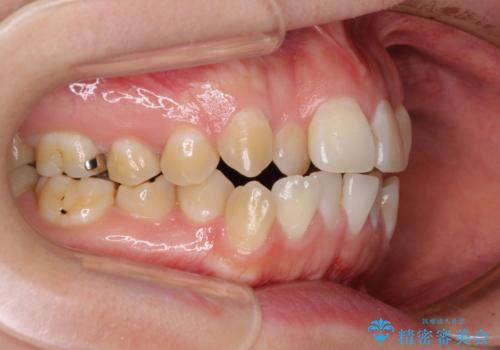

前歯のデコボコはもちろん気になるところですが、舌の突出癖により上下前歯が非接触となっている状態でした。

上下前歯が非接触である開咬は、インビザラインによる治療がお勧めではありますが、しっかりと使う自信がないとのことで、ワイヤー装置にて治療を行うこととしました。

デコボコはあっという間に改善されましたが、開咬の改善に時間がかかりました。

舌の突出癖改善のトレーニングをしっかりと行っていただき、上下前歯が接触する咬み合わせを達成することができました。